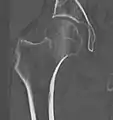

A case demonstrating a possible order of imaging in initially subtle findings:

X-ray showing a suspected compressive subcapital fracture as a radiodense line

CT scan shows the same, atypical for a fracture since the cortex is coherent

T1-weighted, turbo spin echo, MRI confirms a fracture, as the surrounding bone marrow has low signal from edema.